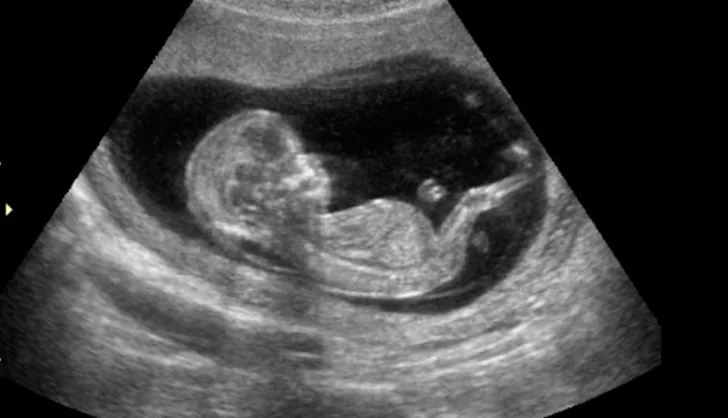

Apenas llegó al hospital, confesó que no había prestado atención a lo que pasaba allí: “Estaba mirando al bebé, no el resto del escaneo”, dijo Hannah Hodgson, que no puede dejar de ver la ecografía.

Este bebé es algo muy importante para Hannah, no solo por ser su hijo, sino porque tiene una historia clínica que le generó grandes preocupaciones: sufrió tres abortos espontáneos y también a sus 18 años sufrió de cáncer.

Sin duda, la imagen de este pequeño “monstruo” resonará por muchos años en su cabeza, y se la mostrará a todos sus conocidos.